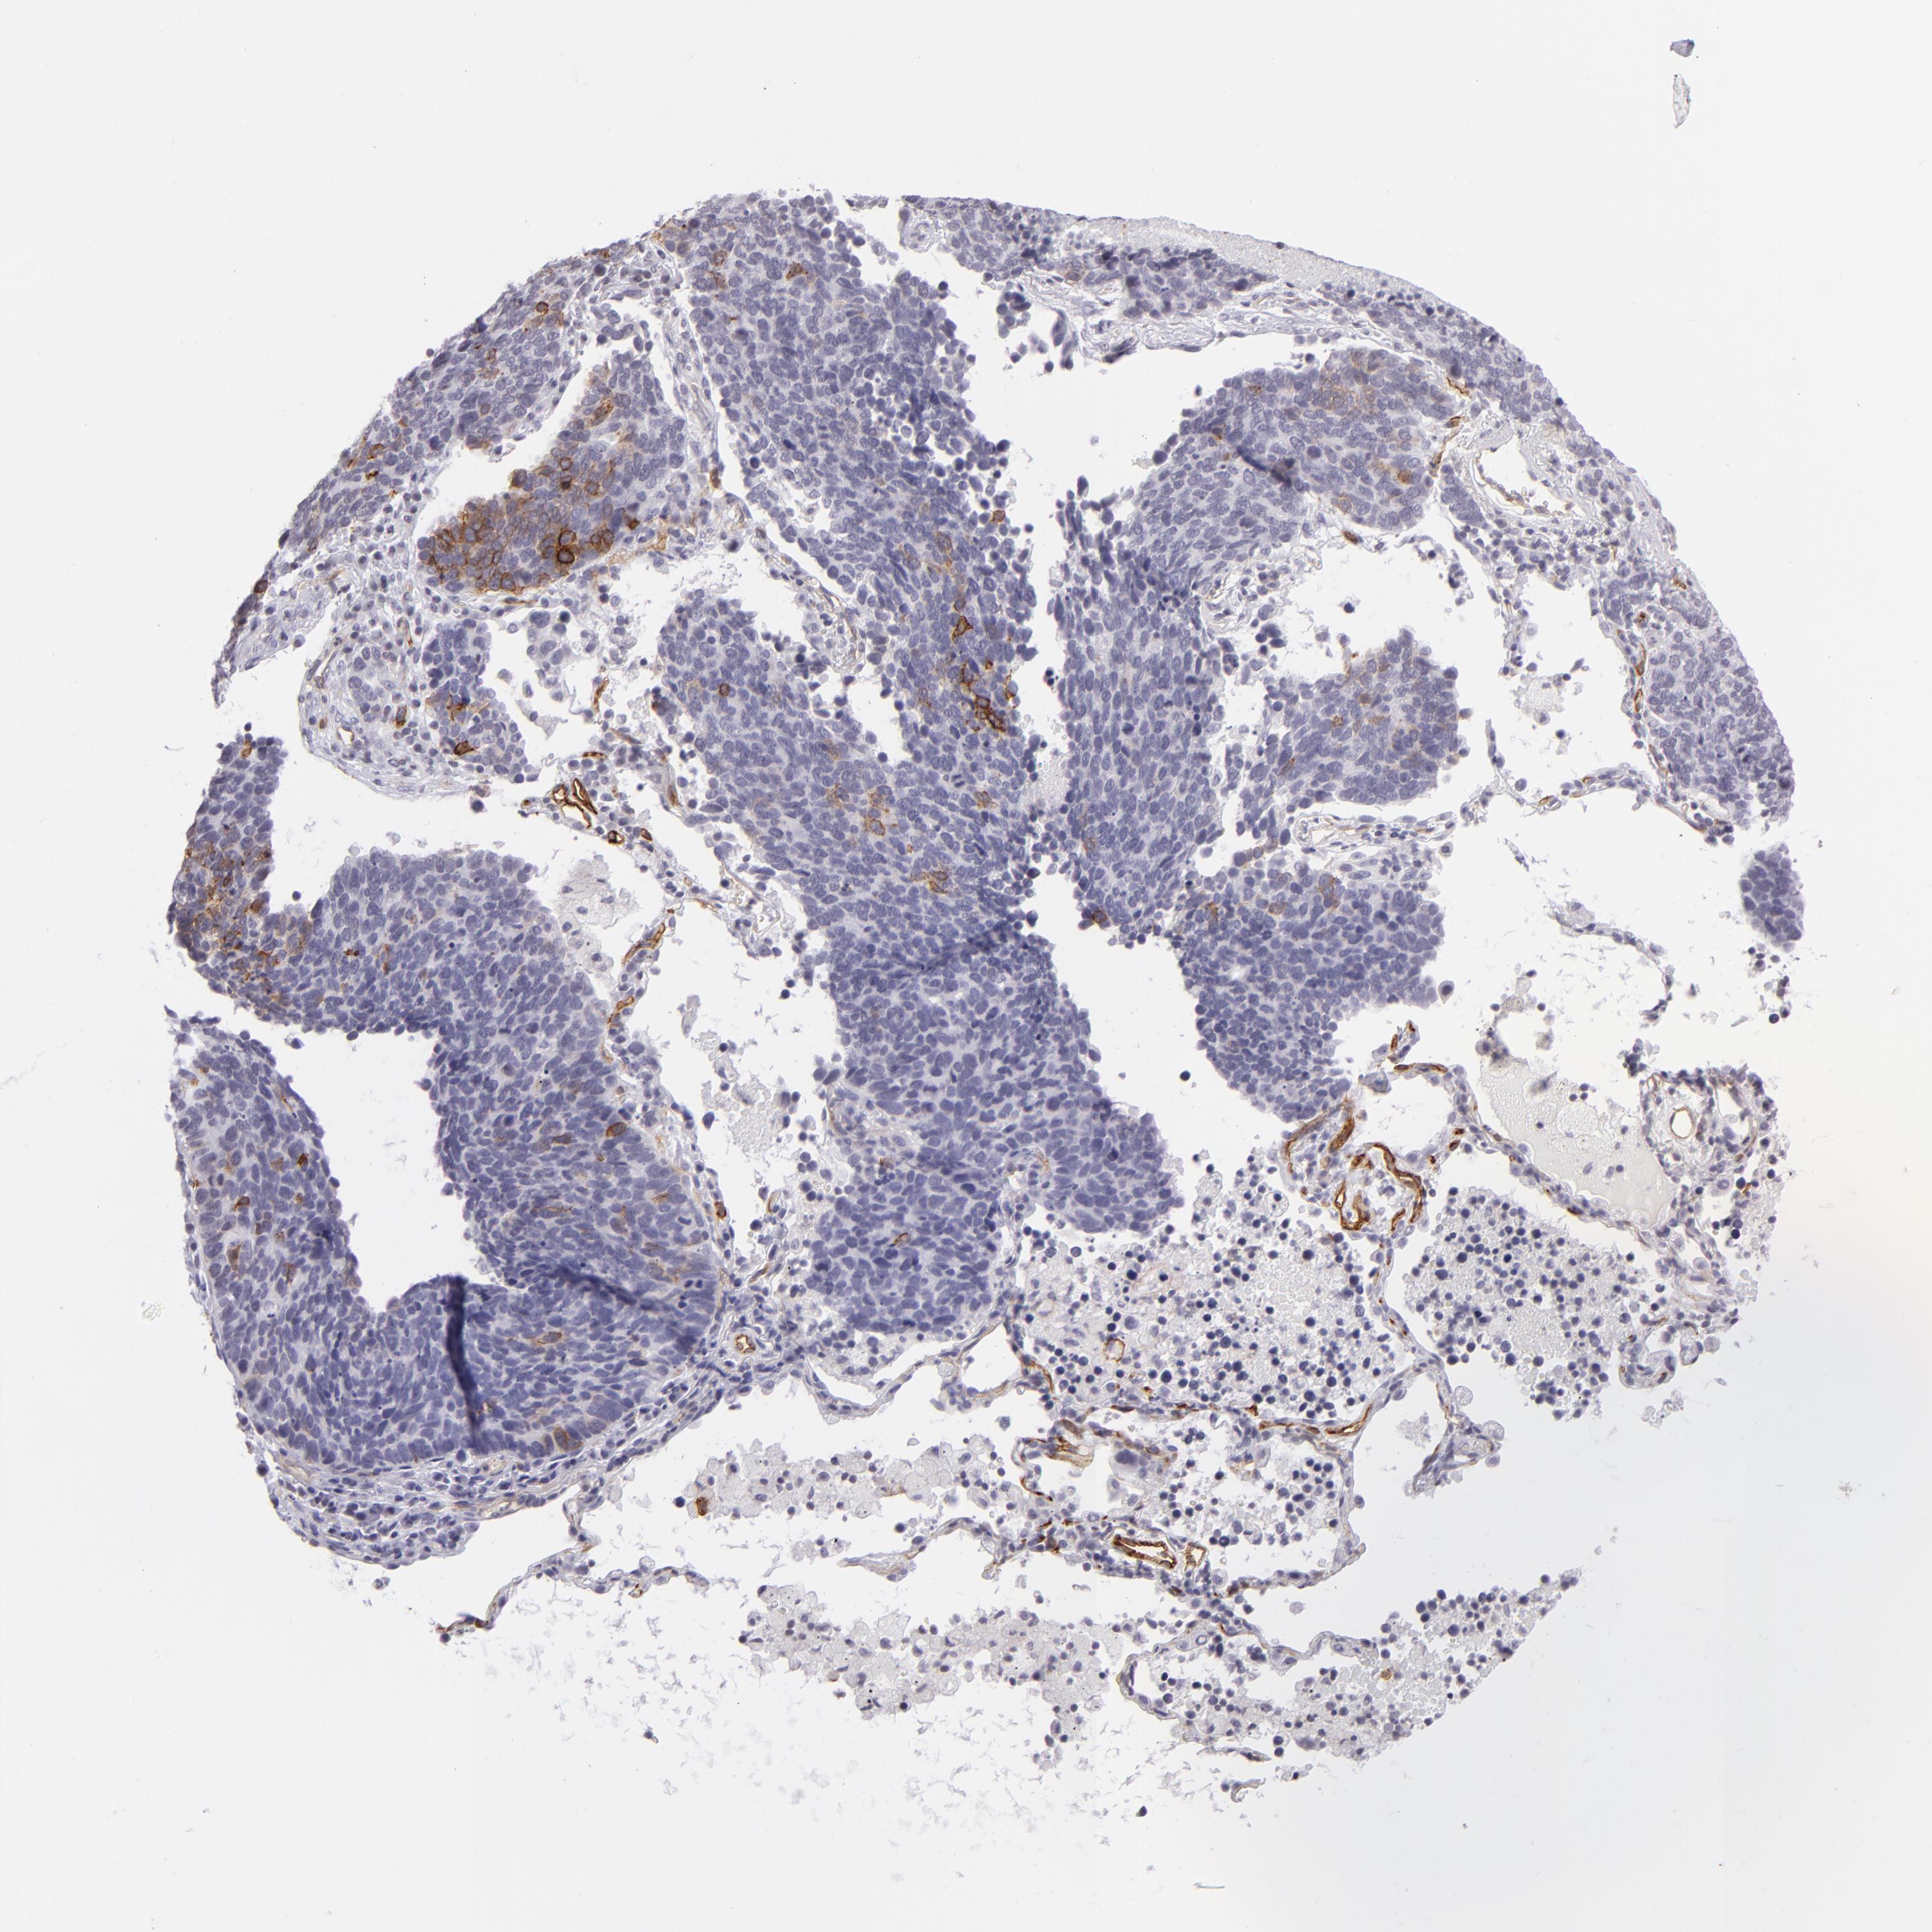

CANCER LUNG CANCER Show tissue menu

Lung cancer

Human cancer

Lung adenocarcinoma

Lung squamous cell carcinoma